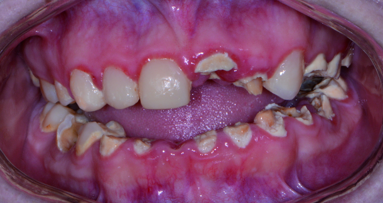

A 38-year-old patient presented with multiple missing teeth. The patient desired the restoration of function and aesthetics. He was undergoing orthodontic treatment. He presented clinically with moderate dental attrition, defective restorations, loss of posterior support, discolouration, mild loss of the VDO and compromised aesthetics (Figs. 1–3). The pre-treatment radiograph showed adequate endodontic obturation, missing mandibular posterior teeth, over-eruption of maxillary posterior teeth and attrition of the incisors. The dentition was free from active dental caries and periodontal probing was within normal limits. The maxillary left molar region bone bed was determined to be inadequate for the placement of dental implants. The mandibular posterior bone bed was diagnosed as Type 2B with sufficient bone density for early implant-loading prosthodontic treatment (Fig. 4).

Figs. 2–5: Pre-treatment intra-oral occlusal view of the maxilla, showing dental attrition and inadequately restored molars. The orthodontic arch wire was broken (Fig. 2). Pre-treatment intra-oral occlusal view of the mandible, showing dental attrition and inadequately restored teeth. A few of the orthodontic brackets were de-bonded from the mandibular incisors (Fig. 3). Pre-treatment orthopantomogram X-ray, showing adequate endodontic fillings, over-eruption of maxillary molars, inadequate occlusal support and inadequately restored teeth. Posterior mandible bone bed was diagnosed as Type 2B (Fig. 4). Completed tooth preparations for full coverage restorations at the approximated treatment VDO. Note the equi-gingival preparation margins. Implants were placed immediately upon completion of crown preparations (Fig. 5).